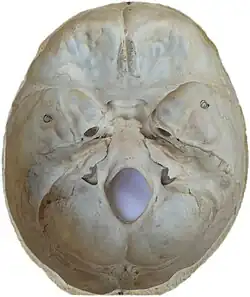

Additional images

-

Middle cranial fossa

Middle cranial fossa

Middle cranial fossa